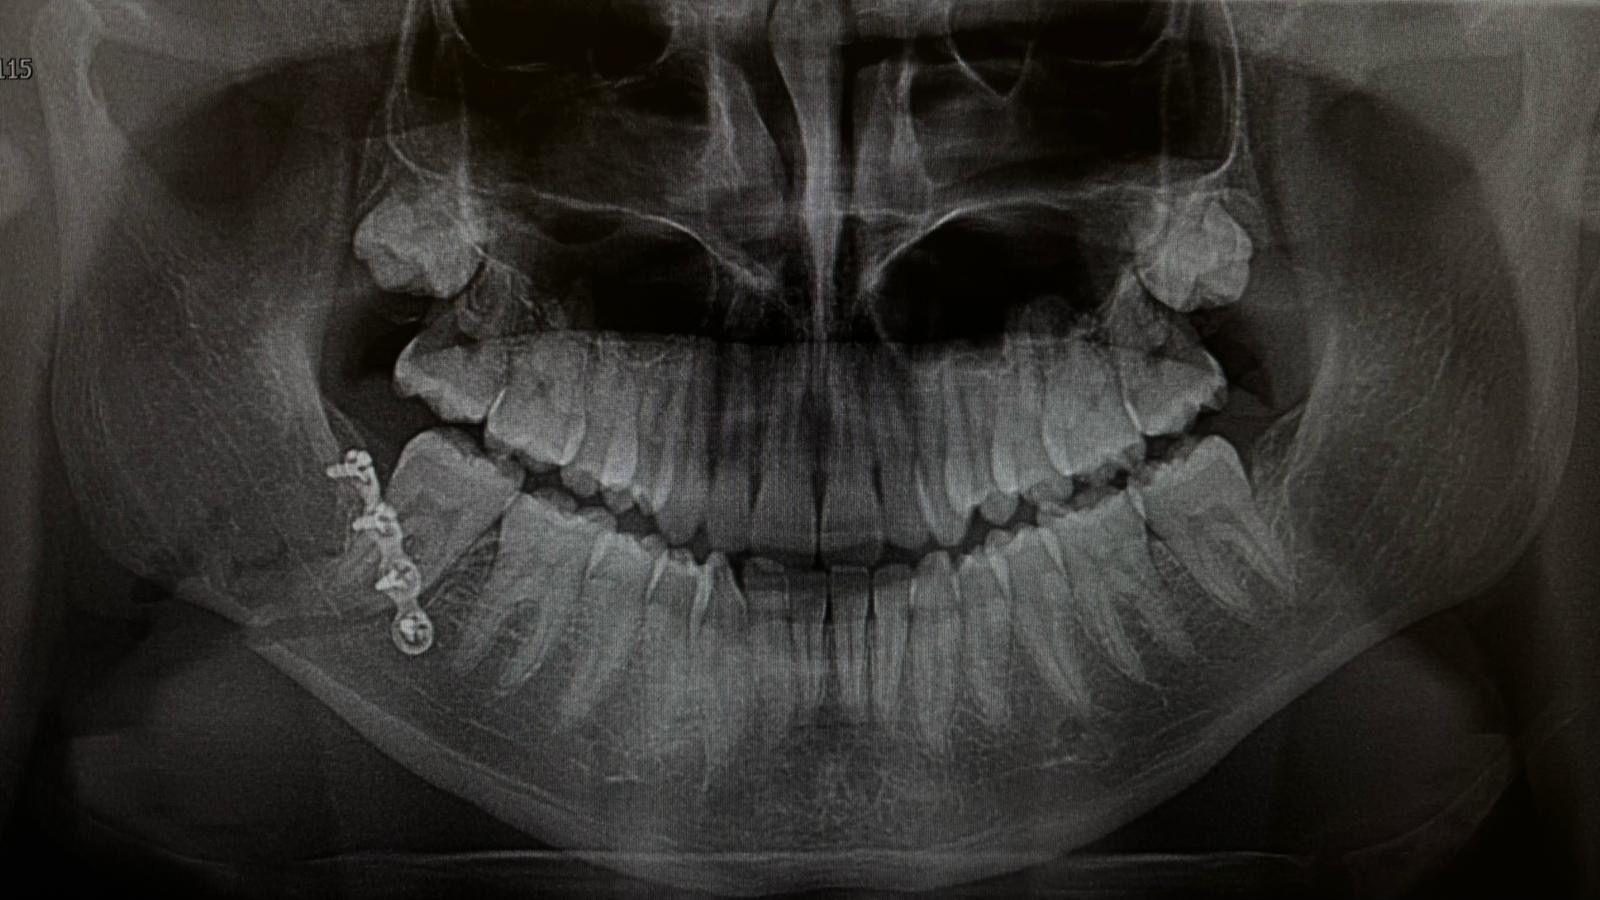

"They threatened to stab him and then, as he tried to leave, he was assaulted from behind and punched in the face. They broke his jaw and he's had to have a plate inserted.

A teenage boy had a metal plate fitted in his jaw following an attack in the park